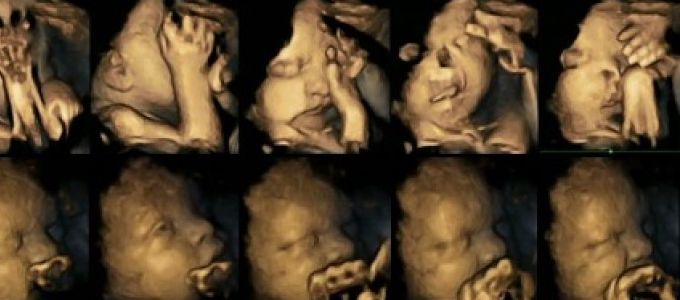

Az anya dohányzásának káros hatásai tükröződhetnek a méhben lévő magzat arcán - mutatták ki négydimenziós ultrahangfelvételek elemzésével brit kutatók.

A Durhami és a Lancasteri Egyetem szakemberei az ultrahangfelvételek vizsgálatakor jelentősen nagyobb mértékű szájmozgást figyeltek meg a dohányzó anyák magzatai esetében, mint az várható a babáknál, akiknek mozgása normális esetben csökkenő ütemű a várandósság utolsó hónapjaiban. A kutatók szerint ennek az lehet az oka, hogy a magzat központi idegrendszere, amely a mozgást általában és különösen az arcmozgást irányítja, nem fejődik abban az ütemben és módon, ahogyan a nem dohányzó anyák magzata esetében.

A szakemberek 20 magzat 80 ultrahangfelvételét vizsgálták, hogy felmérjék a száj- és a tapintómozgást, a felvételek a várandósság négy különböző szakaszában készültek a 24. és a 36. hét közötti periódusban. Négy magzat édesanyja dohányzott napi 14 cigarettát szívva, a másik 16 magzat anyja nemdohányzó volt. Később valamennyi újszülött egészségesen jött a világra. Az Acta Paediatrica gyermekgyógyászati folyóiratban közzétett tanulmányban azt is kimutatták - összhangban más korábbi tanulmányokkal -, hogy az anyai stressznek és depressziónak jelentős hatása van a magzat mozgására, de a száj- és a tapintó mozgások sokkal gyakoribbak voltak a dohányzó anyáknál.